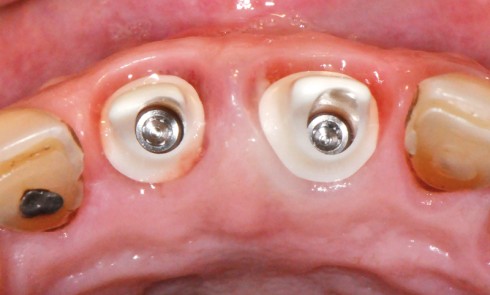

Article réservé à nos abonnés La papille entre deux implants

Nous savons que la position des implants va influencer la qualité et la quantité des tissus inter-implantaires. Lorsque la distance...